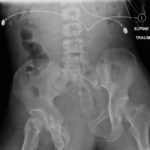

The initial radiograph of the pelvis shows an open-book pelvic fracture deformity with pubic symphyseal dislocation, left greater than right sacroiliac diastases, and fractures of the left superior and inferior pubic rami, right inferior pubic ramus, and left acetabular anterior column. The additional inlet and outlet radiographs of the pelvis after application of a pelvic binder also show an open book fracture with significant improvement of the widened pubic symphysis.